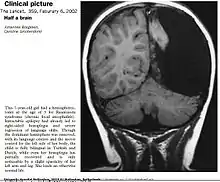

صورة بالأشعة لدماغ أجريت عليه عملية استئصال نصف الكرة المخية.